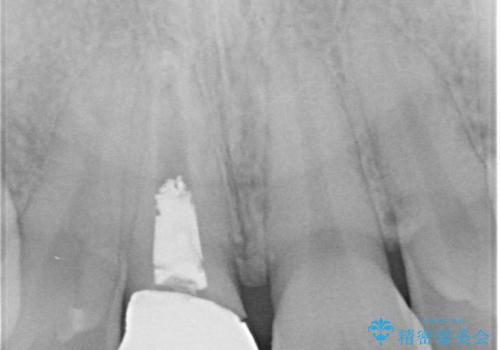

根管の充填物も不十分だったため根管治療からやり直しオールセラミッククラウンで治療を行いました。

根管の中が空洞のままで被せ物と歯のきわも合っておらず適合が悪い状態でした。根尖部付近にはパーフォレーションリペア修復の痕がありました。バイオシーシーラーを使用しシングルポイント法で充填しました。空洞があると細菌が増える環境になってしまうので、根管治療からやり直し、緊密に充填しました。被せ物の見た目も大変満足していただけました。